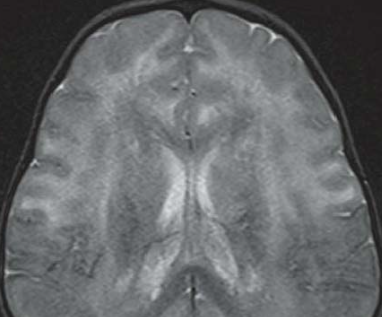

Leucodystrophie Métachromatique

- Confluent, périventriculaire (cornes frontales++)

- Epargne les fibres en U